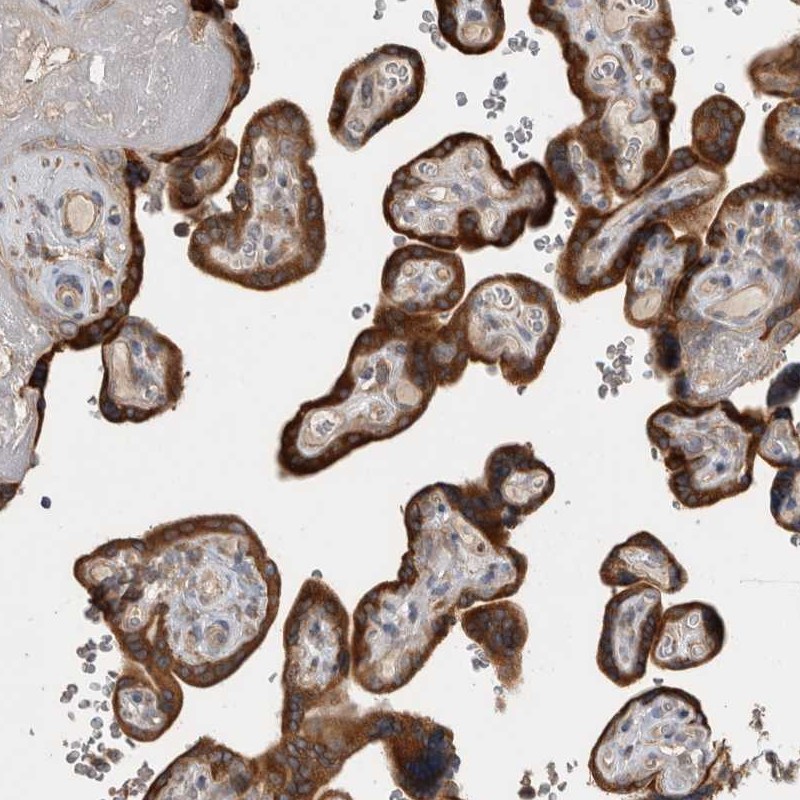

Immunohistochemical staining of human placenta shows strong positivity in trophoblastic cells.